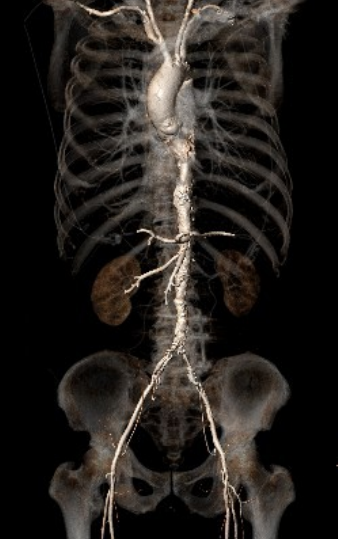

术前CT评估

根部结构:Type1二叶瓣(L-R型),左右之间纤维钙化融合嵴,轻中度钙化伴瓣叶增厚,瓣环:22.0mm,左室流出道 :22.1mm,瓦氏窦:33.1mm,瓣上限制区(supra-8mm):21.5mm,极小心腔。

入路分析:

走形平顺,但主动脉全程多发溃疡样病变,伴夹层及壁内血肿形成;双髂股动脉内径偏小,右侧最小内径2.2mm,左侧最小内径2.6mm,右侧合并血肿及夹层。

左侧颈总动脉走形、内径均可,少量钙化;左右侧锁骨下动脉内径小,最狭窄处分别4.3mm、4.2mm,且伴有不同程度血肿。